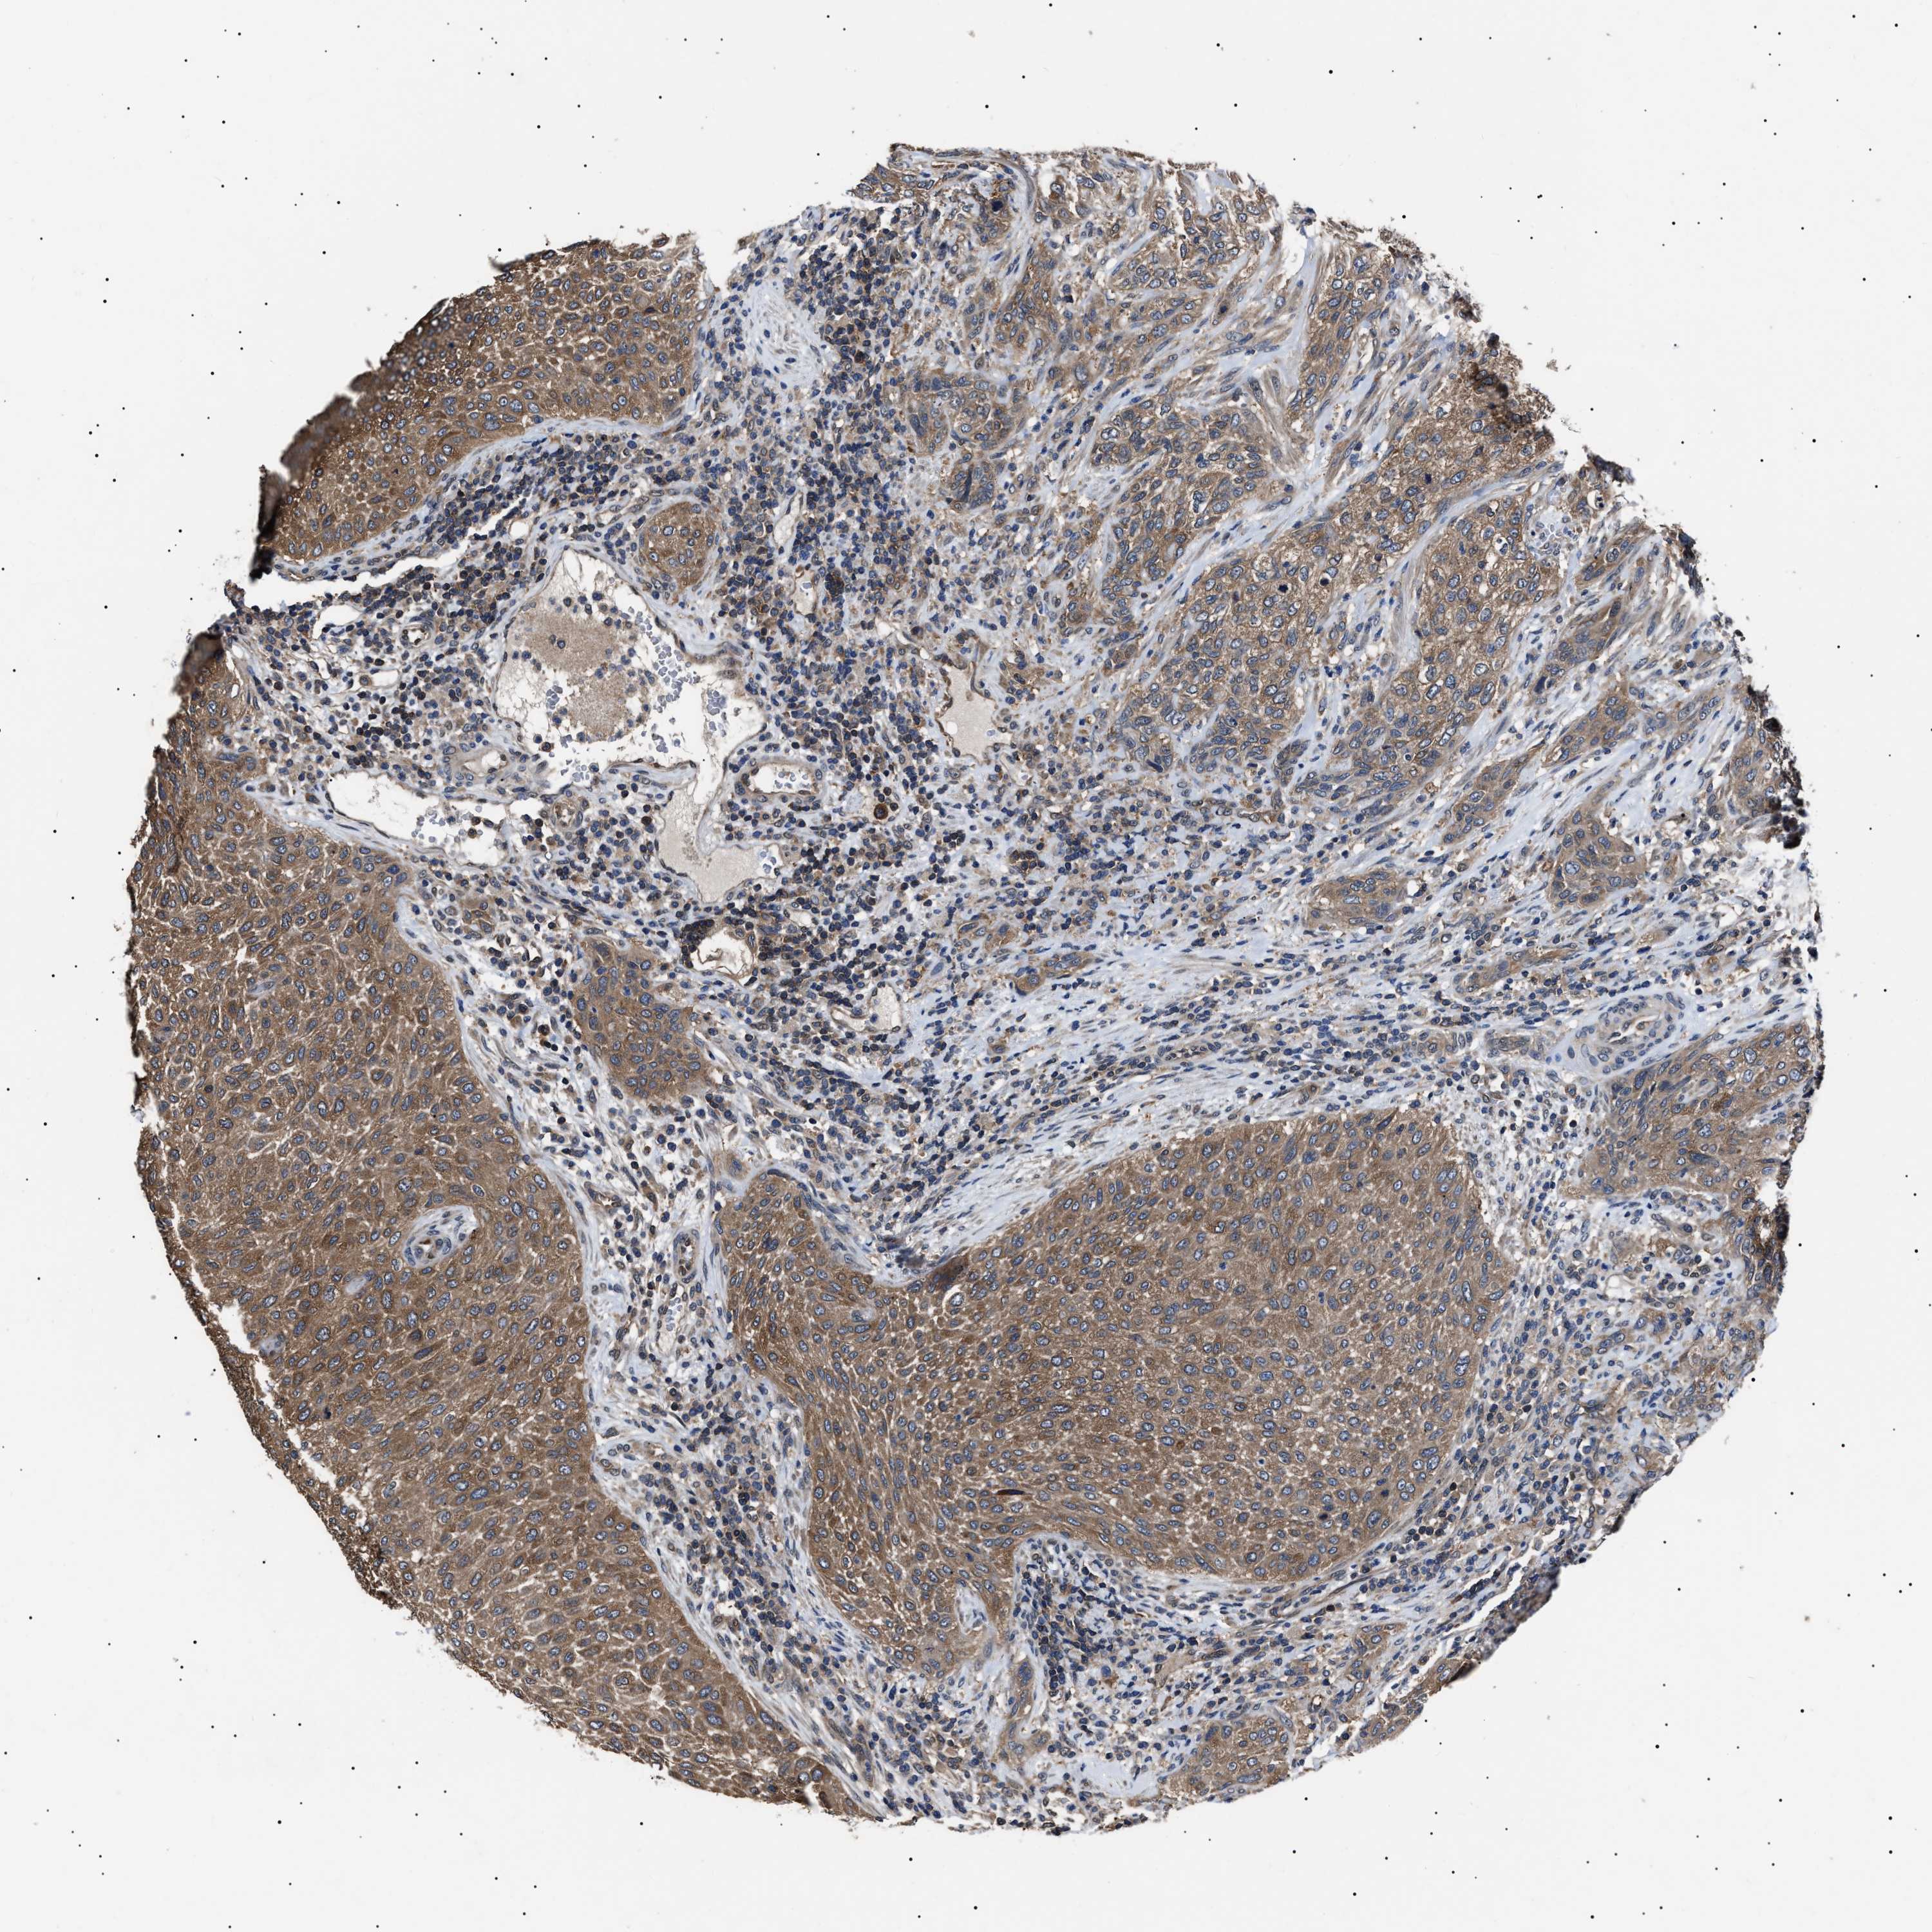

UROTHELIAL CANCER - Protein expressioni

A mouse-over function shows sample information and annotation data. Click on an image to view it in a full screen mode. Samples can be filtered based on level of antibody staining by selecting one or several of the following categories: high, medium, low and not detected. The assay and annotation is described here.

Note that samples used for immunohistochemistry by the Human Protein Atlas do not correspond to samples in the TCGA dataset.

Antibody stainingi

Antibody staining in the annotated cell types in the current human tissue is reported as not detected, low, medium, or high, based on conventional immunohistochemistry profiling in selected tissues. This score is based on the combination of the staining intensity and fraction of stained cells.

Each image is clickable and will lead to virtual microscopy that enables deeper exploration of all samples and also displays staining intensity scores, fraction scores and subcellular localization as well as patient and tissue information for each sample.

Antibody HPA018520

Antibody HPA021051

Antibody HPA029426

Urothelial carcinoma, Low grade

Urothelial carcinoma, High grade